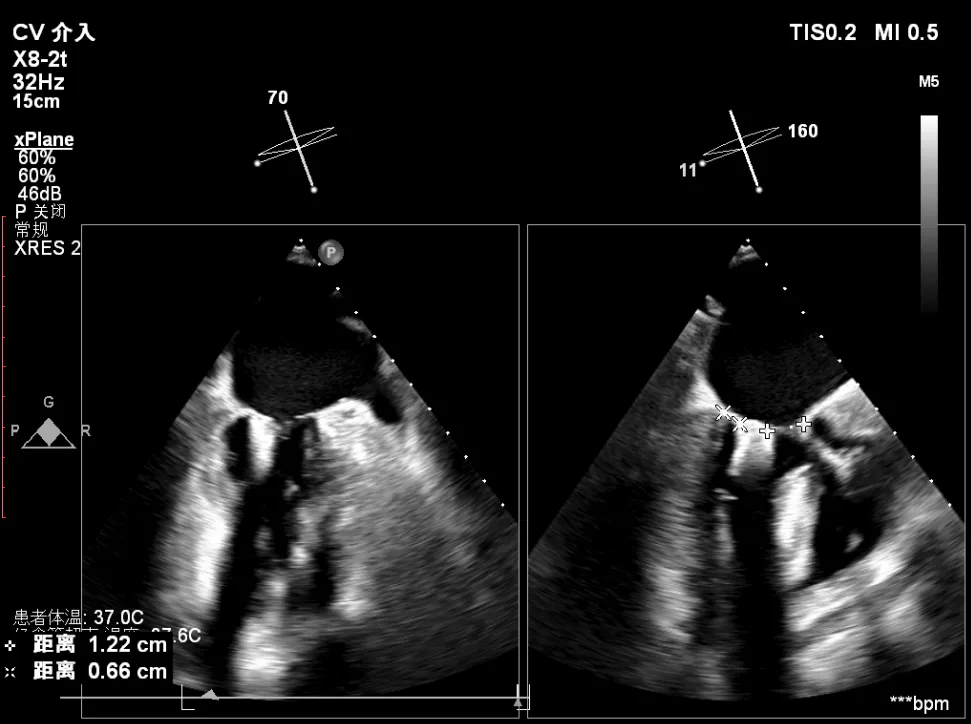

术中超声(关键步骤)

最终在A3P2位置夹合,前叶夹合量10mm,后叶夹合量8mm,剩余瓣口面积3.45cm²,平均跨瓣压差2mmHg,反流基本消除。